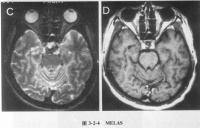

4.脑影像学检查

脑影像学检查

随着脑影像技术的开展与提高,近10年已有许多有关CT及MRI检查本病的报道。我国曾报道对100例氧化碳中毒患者于急性期和出现迟发脑病时进行颅脑CT检查见主要异常为双侧大脑皮质下白质及苍白球或内囊出现大致对称的密度减低区,后期可见脑室扩大或脑沟增宽,异常率分别为41.2%和87.5%脑CT无异常者预后较好,有CT异常者其昏迷时间大都超过48小时。但迟发脑病早期并无CT改变上述CT异常一般在迟发脑病症状出现2周后方可查见,故不如脑诱发电位及脑电图敏感。急性期CT已显示大脑皮质持下白质异常的患者其恢复远较迟发脑病有白质异常者为差,提示两类患者的白质病理改变不同,前者可能兼有髓鞘轴索的损伤后者可能多仅为髓鞘的脱失。MRI在显示一氧化碳中毒脑部病变方面优于CT,二者皆有利于与脑部其他疾病的鉴别诊断